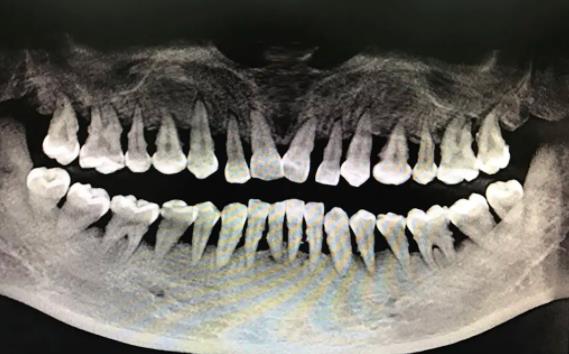

牙槽骨萎縮,搖搖欲墜的牙齒

因為(wei) 口腔清潔不好會(hui) 殘留食物殘渣,從(cong) 而會(hui) 滋生細菌形成牙菌斑,牙菌斑一段時間後形成牙結石,對牙齒周圍的牙齦和牙槽骨組織形成刺激,使其骨肉分離,從(cong) 而出現牙齒鬆動甚至脫落。

而且,牙周炎引起的掉牙和蛀牙、外傷(shang) 等造成的缺牙通常不一樣,一旦有一顆牙齒鬆動脫落了不及時治療,很快就會(hui) 有第二顆、第三顆,直到出現一排牙齒掉光的連鎖反應。因此,牙周炎掉牙可能是一排排的掉,這並不是嚇唬人的。

牙周炎是牙齒周圍支持組織的炎症。而牙齒周圍支持組織,比如牙槽骨和牙齦,這對於(yu) 牙齒來說,就像是一座房子的地基一樣,隻有地基穩固長久,也才能保障上麵的房子是沒問題的。如果地基出現了問題,上麵的房子再漂亮都會(hui) 倒塌。